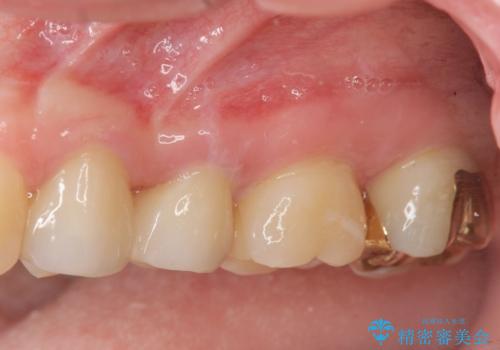

放置された虫歯 小矯正+歯周外科による保存処置